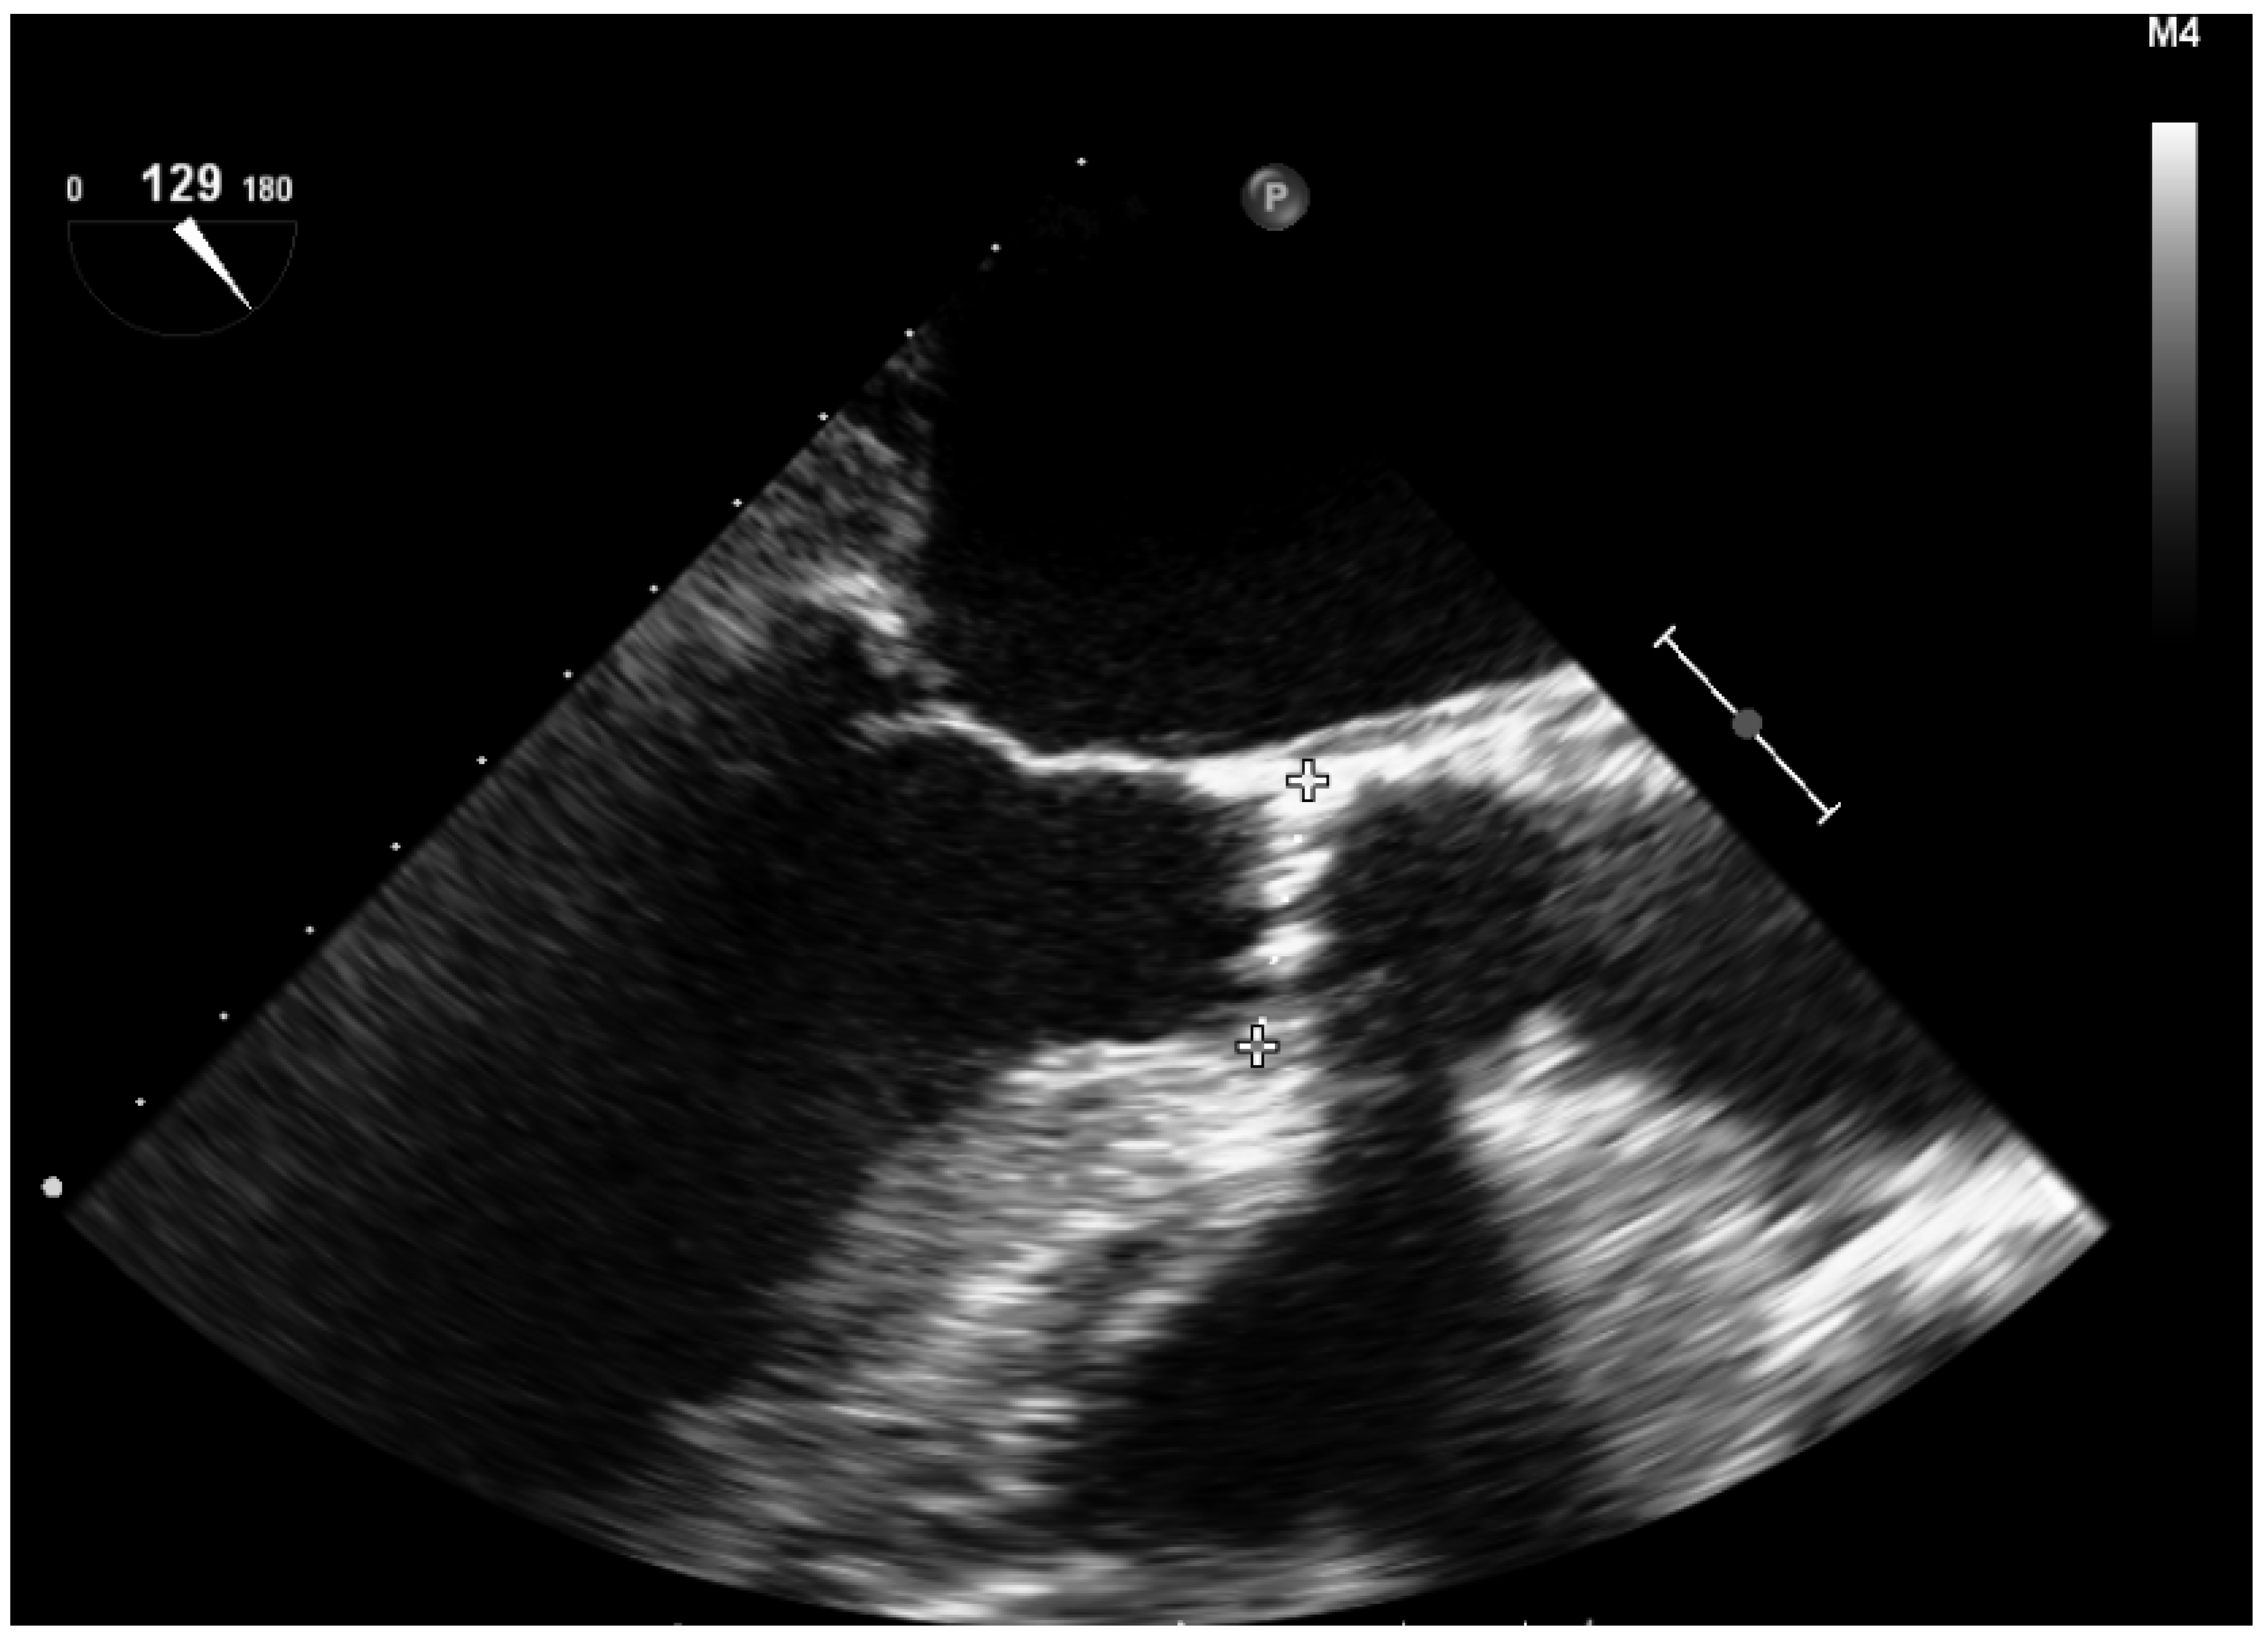

Figure 3.

Aortic transvalvular gradients obtained from deep within the transgastric plane.